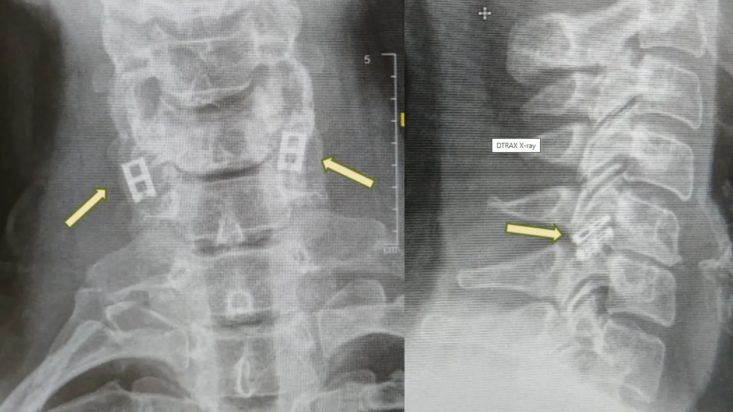

Προς το παρόν, οι τραυματισμοί του νωτιαίου μυελού δεν μπορούν να θεραπευτούν πλήρως, επομένως η θεραπεία επικεντρώνεται στη σταθεροποίηση του ασθενούς, την πρόληψη περαιτέρω προβλημάτων και τη μεγιστοποίηση της λειτουργικότητας. Η επείγουσα φροντίδα περιλαμβάνει συχνά την ακινητοποίηση της σπονδυλικής στήλης, τη μείωση της φλεγμονής και σε ορισμένες περιπτώσεις τη χειρουργική επέμβαση για αποκατάσταση καταγμάτων ή την ανακούφιση από πίεση.

Σε αντίθεση με άλλους ιστούς, οι νευρώνες του νωτιαίου μυελού δεν μπορούν να αναγεννηθούν φυσικά, και με την πάροδο του χρόνου, ο ουλώδης ιστός εμποδίζει τα εναπομείναντα σήματα. Η νέα διαδικασία στοχεύει στην αντικατάσταση του κατεστραμμένου τμήματος με εργαστηριακά καλλιεργημένο νωτιαίο μυελό που συγχωνεύεται με τον υγιή ιστό πάνω και κάτω από το σημείο του τραυματισμού.